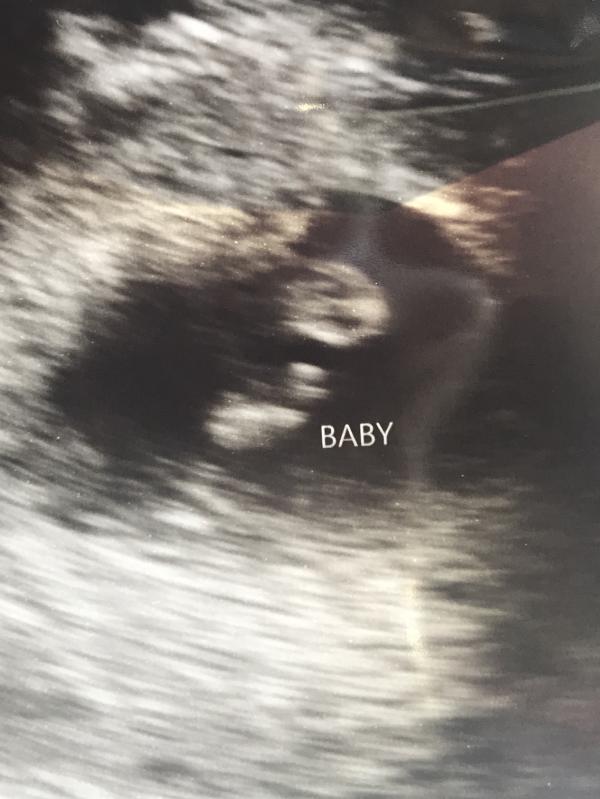

Baby Collin, snug as a bug, measuring 6weeks 6 days, heart rate of 141, due May 9, 2019 🙌🙌 God is so good!!

Thanks ladies!! My uterus is apparently a little wonky after having my daughter. Even with a transvaginal ultrasound this is the best image they could get. They couldn’t find my left ovary. And they almost couldn’t get a reading on the heart beat but we saw the flicker. They got this picture at the vey end and measured the heart rate 💙❤️💙❤️💙❤️